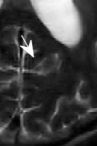

While the scenario of longitudinal studies is fundamentally different from dynamic MRI in many aspects, we still find that similarity across time points exists in many cases. Figure 1 shows an example of the same axial slice taken from multiple scans acquired from a patient with Optic Pathway Glioma (OPG), demonstrating a relatively slow growing tumor pattern. The bottom row of the figure shows the representation of each time point in Daubechies-4 wavelet transform (Daubechies et al., 1992), which is widely used as a sparse transform for brain MRI. The similarity between image slices acquired at several time points is clearly demonstrated. Moreover, the representation of the images in the wavelet domain is sparse, and the locations of the dominant wavelet coefficients (a.k.a the support of the image in the wavelet domain) are similar across the patient’s time points.